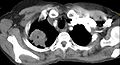

- Scanner thoracique